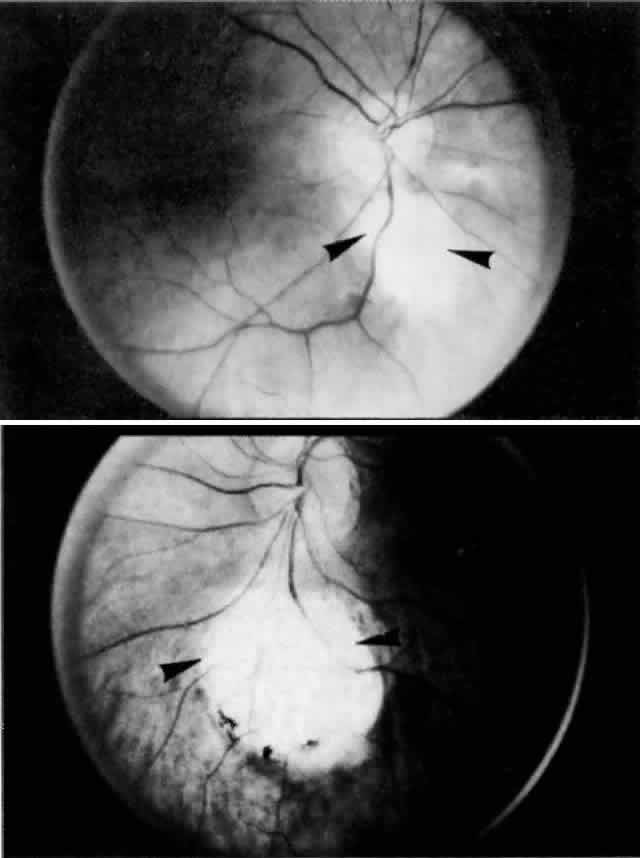

in a healthy globe.17–20 Drusen, ophthalmoscopically visible deposits present between the RPE basement

membrane and the inner collagenous layer of Bruch's membrane, are

more prevalent with increasing age (Fig. 9). A morphometric study of Bruch's membrane, the choriocapillaris, and

the choroid in aging was performed by Ramrattan and associates21 in eyes obtained from patients ranging from 6 to 100 years old with normal

maculae. The findings revealed that the thickness of Bruch's

membrane in the normal macula increases by 135% between the 1st and 10th

decades of life (from 2 to 4.7 μm), while the choriocapillaris

density and diameter and the choroidal thickness generally decreased in

a linear fashion in the same time interval. Statistical analysis of

the morphometric data showed that the thickness of Bruch's membrane

was directly related to age alone and that there was no relationship

between age-related atrophy of the choriocapillaris and changes in Bruch's

membrane thickness.  Fig. 9. Solitary nodular drusen (arrow) resting on inner surface of Bruch's membrane. (H & E, × 63) Fig. 9. Solitary nodular drusen (arrow) resting on inner surface of Bruch's membrane. (H & E, × 63)